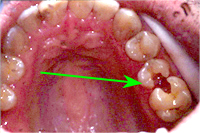

Um Riesenlöcher (Karies) in den Zähnen zu vermeiden (Abb. 1), geben wir Ihnen auch eine umfassende Information über Ernährung. Wir erklären Ihnen die Zusammenhänge, wann der Genuss von Süssigkeiten für Ihre Zähne verheerende Folgen haben kann und unter welchen Umständen überhaupt keine Zahnschäden entstehen müssen. Ist eine Karies allerdings einmal vorhanden, muss sie unbedingt behandelt werden. Wie, das erklären wir Ihnen gerne im Kapitel Konservierende Zahnmedizin.